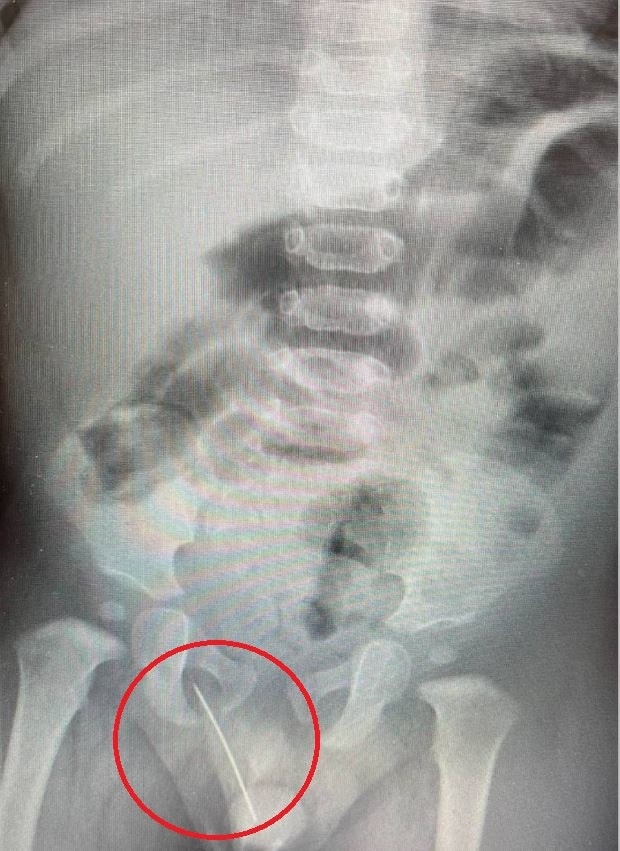

Врачи Детского центра им. Рошаля извлекли иглу 6 см из годовалого ребенка

После экстренного проведения рентгенографии врачи диагностировали инородное тело металлической плотности, расположенное в мягких тканях между мошонкой и прямой кишкой - мальчик, вероятно, случайно сел на иглу.